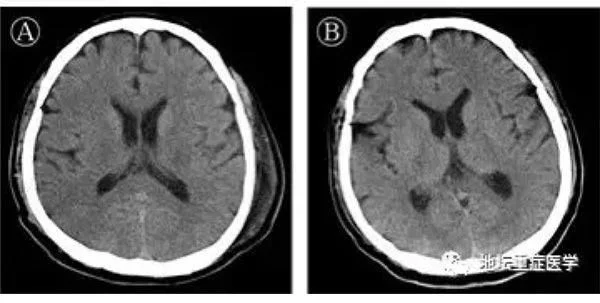

据首都医科大学附属北京地坛医院3月4日公布,此前的2月25日,首例新冠肺炎合并脑炎患者从该院顺利出院。北京地坛医院ICU主任刘景院主持该患者的救治工作,他提醒:患者出现意识障碍,一定要考虑病毒有可能攻击中枢神经系统。目前来说,新冠肺炎患者可合并重度呼吸窘迫综合征(ARDS)、心肌损害、凝血功能异常、肾脏损伤、肝脏损害等多脏器损害,但尚未发现有中枢神经系统受累的报道,此病例报道在全球尚属首例。而此前针对SARS(严重急性呼吸综合征)、MERS(中东呼吸综合征)的研究也均有显示,引发这两种疾病的冠状病毒同样有引起中枢神经系统损伤的案例。据北京地坛医院介绍,自今年1月12日收治2例新冠肺炎疑似病例(1月20日确诊),截至3月4日7时,该院累计收治新冠肺炎患者150人,其中上述患者是唯一1例新型冠状病毒性肺炎并脑炎患者。据介绍,该患者56岁,1月24日以新冠肺炎、危重型、呼吸衰竭收入院。入院后给予联合干扰素雾化、抗病毒治疗,预防细菌感染,并给予中医辨证用药。未见好转,高热,乏力,呼吸困难逐渐加重。1月27日(起病第10天)胸部CT显示双肺磨玻璃密度影范围扩大,部分实变影。短暂予经鼻高流量吸氧,其呼吸窘迫无缓解,烦躁不安,呼吸50次/分,氧分压85%,在ICU进行气管插管,按照ARDS的呼吸通气原则进行机械通气。治疗96小时后(起病第14天),患者出现颌面及口角频繁抽搐,伴持续呃逆,医生查体发现颈抵抗阳性,双侧瞳孔等大等圆,对光反射迟钝,四肢肌张力升高,双侧膝反射亢进,双侧巴氏征及踝阵挛阳性,头颅CT颅内未见异常,测脑脊液压力大于330mmH2O,脑脊液外观无色清亮,生化检测无异常。北京地坛医院重症医学科、检验科及中国疾控中心传染病所联合工作组对采集的脑脊液标本进行宏基因组二代测序、鉴定可能的感染病原体过程中,排除了其他病原体,获得了新冠病毒基因组序列。通过基因测序证实脑脊液中存在新冠病毒,临床诊断病毒性脑炎。随后,医护人员经过对其14天机械通气和甘露醇控制颅压、咪唑安定控制抽搐、丙种球蛋白及甲基强的松龙抗炎等针对病毒性脑炎的处理,观察患者肺病影像学逐渐好转,神经系统症状消失。2月10日(起病第24天)在充分评估患者呼吸及神经功能后拔出气管插管,给予鼻导管吸氧。2月18日(起病第32天)转出重症监护室,到新冠确诊病房继续接受治疗。刘景院提醒,在临床观察中,不乏有颈抵抗,病理征阳性,突发意识障碍甚至昏迷的病例存在,面对此类患者,需要警惕新冠病毒感染可累及中枢神经系统,及时进行脑脊液等相关检查,并完善脑脊液SARS-CoV-2核酸及基因测序等工作,为更全面了解COVID-19做出探索,并积极处理相关神经系统并发症,从而进一步降低危重病人的病死率。值得注意的是,就在3月3日国家卫生健康委员会发布的《新型冠状病毒肺炎诊疗方案(试行第七版)》(以下简称“第七版”)中,其中即增加了病理改变,除肺脏、脾脏、肺门淋巴结和骨髓、心脏和血管、肝脏和胆囊、肾脏之外,也同时提及“脑组织充血、水肿,部分神经元变性”。